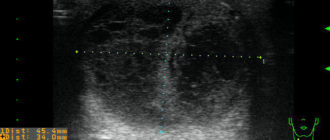

Узи признаки макрофолликулов и кисты левой доли

Признаки и причины появления макрофолликулов щитовидной железы По данным Всемирной Организации Здравоохранения заболевания щитовидной